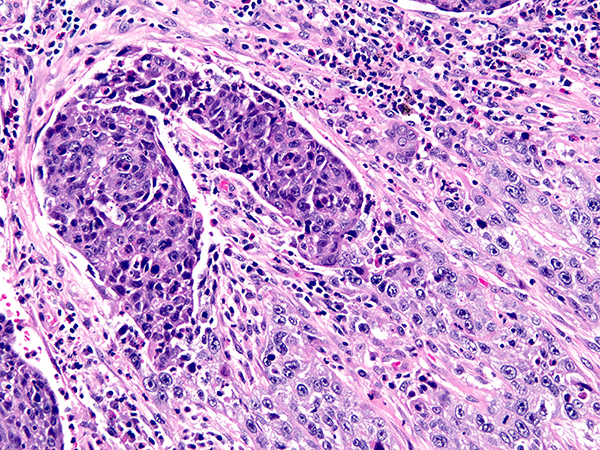

Clinical History: A 60-year-old man with a lung mass underwent EBUS-TBNA followed by lobectomy and mediastinal lymph node dissection for lung cancer. Sections from the lung mass are shown in Figures 1 and 2. A section of the background lung is shown in

Figure 3. Mediastinal lymph nodes are in Figures 4-6.

Lung: poorly differentiated squamous cell carcinoma and chronic lymphocytic B-cell leukemia/small lymphocytic lymphoma

Both p63 and p40 can be used as squamous markers in the subtyping of non-small cell lung carcinomas that cannot be subtyped on H&E, especially when staining is strong and diffuse. Both markers have equivalent sensitivity for squamous cell carcinoma, being positive in essentially all poorly differentiated squamous cell carcinomas of the lung. In terms of specificity, p40 is superior to p63, in that it stains a lower proportion of adenocarcinomas (3% vs. 31%). Even with this increased specificity, rare cases of lung adenocarcinoma can stain focally with p40. Neither p63 nor p40 have a role in determining site of origin of squamous cell carcinoma.